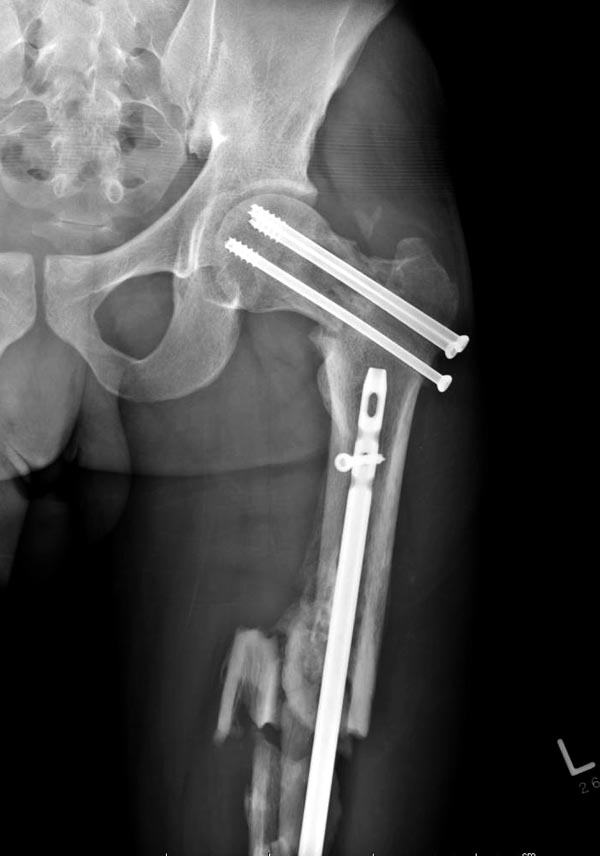

Здесь выставлен ренгенограммы больного, ему 21, травму получил в

результате высокоскоростной погони на украденной машине, которая

закончилась смертью трех остальных“боевых комрадов”. Начатую коллегой

открытую операцию на шейке пришлось закончить мне, установкой винтов и

ретроградной фиксацией бедра. Выписка в обычное сроки и наблюдался

амбулаторно. Каждый раз напоминали о возможности осложнений ввиде

несращения! По истечению 4 месяцев появились признаки варусной

деформации. На СТ срезах несращение шейки и бедра. Риминг, замена на

более толстый гвоздь и вальгусная остеотомия.